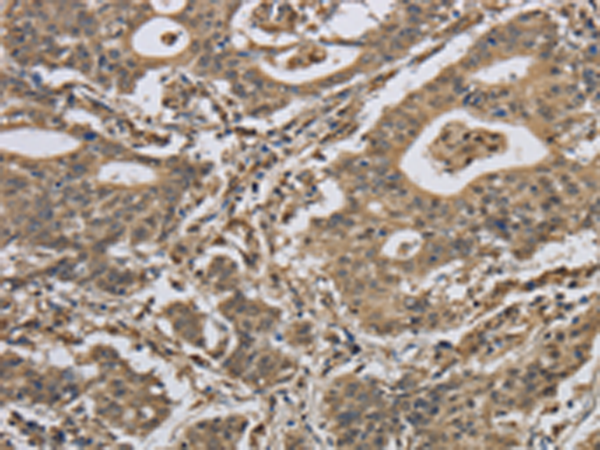

分类: 科研抗体货号: P11858别名: RANBP8应用: IHC反应种属: Human, Mouse